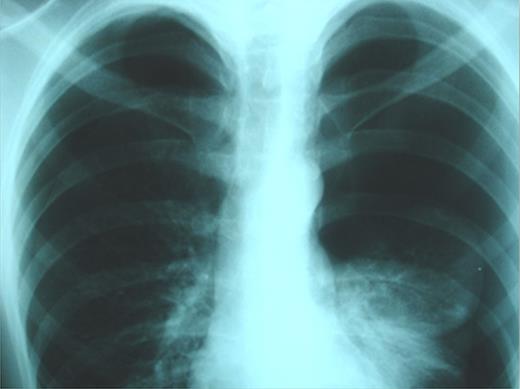

On emergency basis, the patient was managed with bilateral tube thoracostomy through the fifth intercostal spaces. During hospitalization, both lungs were gradually expanded; the use of continuous aspiration was necessary for a couple of days, in order to achieve complete expansion of the left lung (Fig. 2). Both chest tubes were removed on the fifth day of hospitalization. Next day the plain X-ray revealed recurrence of pneumothorax on the left side (Fig. 3). A chest tube was reinserted. Continuous suction was used and complete expansion of the left lung was succeeded. The tube was removed after 5 days; no recurrence took place at this time. During the next 3 days the patient remained under observation; serial physical examinations and chest X-rays were normal and the patient was discharged home.

Recurrence of pneumothorax on the left side after removing the chest tube.